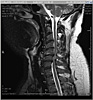

MRI_6_sm

MRI of the cervical spine. Notice the bulges in the discs pressing on the spinal cord between vertebrae C5-C6 and C6-C7. Also note the whitish areas in the spinal cord where it’s compressed.